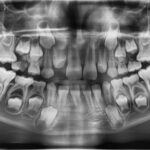

Eruzione ectopica del primo molare permanente: l’importanza della diagnosi precoce Premium

La diagnosi precoce nell'eruzione ectopica del primo molare permanente, associata a un regolare monitoraggio durante la dentizione mista, è determinante nel prevenire complicanze occlusali e nel favorire uno sviluppo armonico delle arcate dentarie e della crescita facciale.